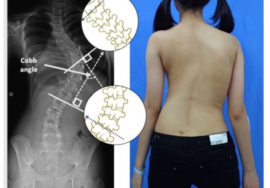

في إطار التوعية بالجنف، من المهم فهم مشكلة الجنف عند البالغين، خاصةً مع التقدم في العمر. الجنف هو انحناء غير طبيعي للعمود الفقري يمكن أن يسبب آلامًا مزمنة ويؤثر على جودة الحياة. في هذا المقال، سنوضح علامات الجنف لدى البالغين، أنواعه، وأهم طرق الكشف المبكر والفحص المنزلي، لتكون على دراية بكيفية التعرف عليه والتصرف بسرعة.

يبدأ هذا النوع منذ مرحلة الطفولة أو المراهقة ويستمر حتى البلوغ. بعد اكتمال نمو العظام، قد يتوقف تطور الانحناء، لكن مع تقدم العمر، يمكن أن يزداد الانحناء نتيجة تدهور الأقراص والغضاريف بين الفقرات. يعرف هذا النوع أحيانًا باسم الجنف التنكسي عند البالغين.الجنف التنكسي الجديد (De-Novo Scoliosis)

يظهر هذا النوع لأول مرة عند البالغين دون تاريخ سابق للجنف. يحدث غالبًا بسبب تآكل الغضاريف والمفاصل بين الفقرات، خاصة في المنطقة القطنية. في بعض الحالات، يصعب التمييز بينه وبين النوع الأول، خصوصًا إذا لم يتم تشخيص الانحناء في سن مبكرة.